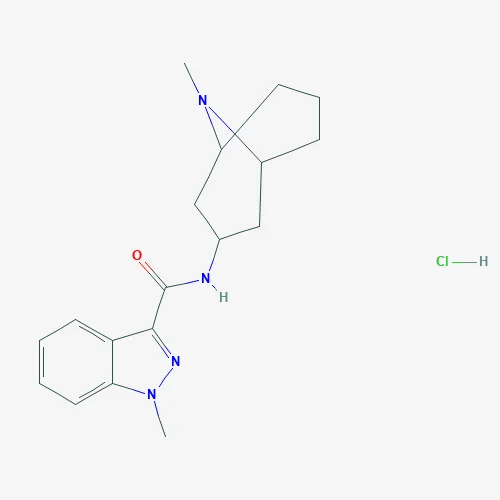

Quick Details Port: Any main port of China Payment Terms: L/C,D/A,D/P,T/T,Western Union,MoneyGram,Alipay, Wepay Supply Ability: 100 Ton/Tons per Month Water: 0.5% Max. Other Names: methyl-lithiu Disregard limit: 0.0005% Purity: 99%min Total Impurity: 0.2% Max. Sulfated ash: 0.1% Max. Identification: Infrared Absorption Appearance: Solid Form Heavy metals: 10ppm Max CAS No.: 917-54-4 Assay: HPLC Structure Identification: H-NMR&LC-MS Type: Agrochemical Intermediates,Dyestuff Intermediates,Flavor & Fragrance Intermediates,pharmaceutical intermediates,Syntheses Material Intermediates Content: 99.0% to 101.0% EINECS No.: 213-026-4 Test method: HPLC-ESI-MS MF: CH3Li Application: Pharm/Chem Industries Delivery Detail: 10 Days Packaging Detail: 25kgs/Drum; 200kgs/Drum Product Description Our Referance Specification, for more details, pls contact us for COA,MSDS and certification: Email:support(at)dideu.com(Skype), sales(at)dideu.com Telephone:+86-29-88380327 mobile&whatsapp&viber:+8618192503167;skype:jacky.zhou(@)dideu.com Item Standard Test Results Identification A.H-NMR:Comply with the structure Complies B.LC-MS:Comply with the structure Complies C.The IR spectrum of sample should be identical with that of reference standard; Complies D.HPLC-ESI-MS The retention time of the major peak in the chromatogram of the Assay preparation corresponds to that in the chromatogram of the Standard preparation, as obtained in the Assay. Complies Loss on drying ≤0.5% 0.11% Heavy metals ≤10 ppm <10ppm Sulphated ash ≤0.2%, determined on 1.0 g. 0.009% Related substances Unspecified impurities: for each impurity […]